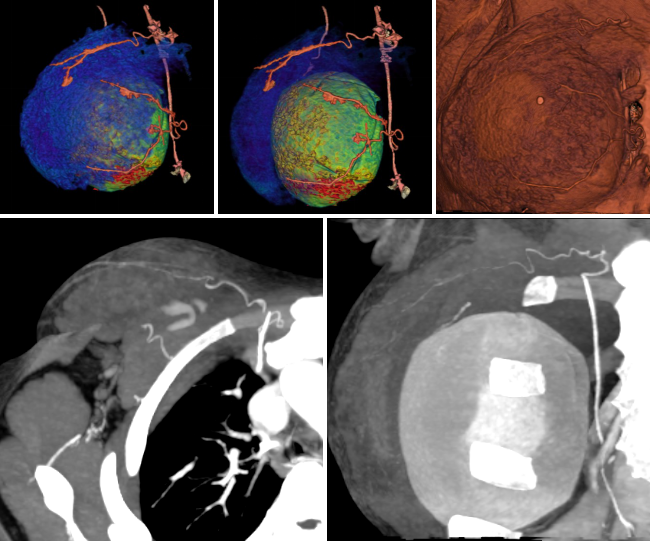

病例一 女,30歲, 行巨乳癥術(shù)前CT檢查。

綠色血管是鎖骨下動(dòng)脈和內(nèi)乳動(dòng)脈。 紫色的是從內(nèi)乳動(dòng)脈上面發(fā)出來(lái)的胸廓內(nèi)動(dòng)脈, 主 要是滋養(yǎng)乳腺的內(nèi)上象限。 紅色血管是從腋動(dòng)脈發(fā)出的胸廓外動(dòng)脈, 滋養(yǎng)乳房的外下象限。

病例二 女,28歲, 胸部塑型術(shù)后復(fù)查。

運(yùn)用640層寬體探測(cè)器CT設(shè)備小焦點(diǎn)、高清模式的超低劑量智能追蹤法及動(dòng)態(tài)灌注掃描方式,通過(guò)了解鎖骨下動(dòng)脈、胸廓外動(dòng)脈、胸廓內(nèi)動(dòng)脈、腹淺動(dòng)脈以及遠(yuǎn)端分支,和所支配的從淺表到深部組織的供 血,方便對(duì)巨乳癥、乳腺癌皮瓣移植術(shù)后及胸部塑形等患者的精準(zhǔn)手術(shù),保證末梢循環(huán)和皮膚組織的供血,減少遠(yuǎn)端末梢組織的壞死以及并發(fā)癥。給臨床醫(yī)生進(jìn)行手術(shù)入路指導(dǎo)。